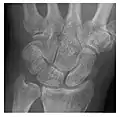

Triquetral fracture usually occurs on the dorsal aspect by impingement from the ulnar styloid or avulsion of strong ligamentous attachment. The dorsal avulsion fracture or "chip fracture" appears as a small bony fragment on the dorsal aspect of the triquetrum and is best detected on the lateral view(Figure 4). When radiography is negative in patients with high suspicion of a fracture, both MRI and MDCT will be of value. However, it has been shown that MRI is superior for detecting trabecular fractures in carpal bones.

a

b

Figure 4: Dorsal triquetral fracture of the left wrist in a 30-year-old man after a trauma. (a) Anteroposterior radiograph shows a normal appearance. (b) Lateral radiograph of the same wrist demonstrates a chip fracture off the dorsal aspect of the triquetrum (arrow).[1]